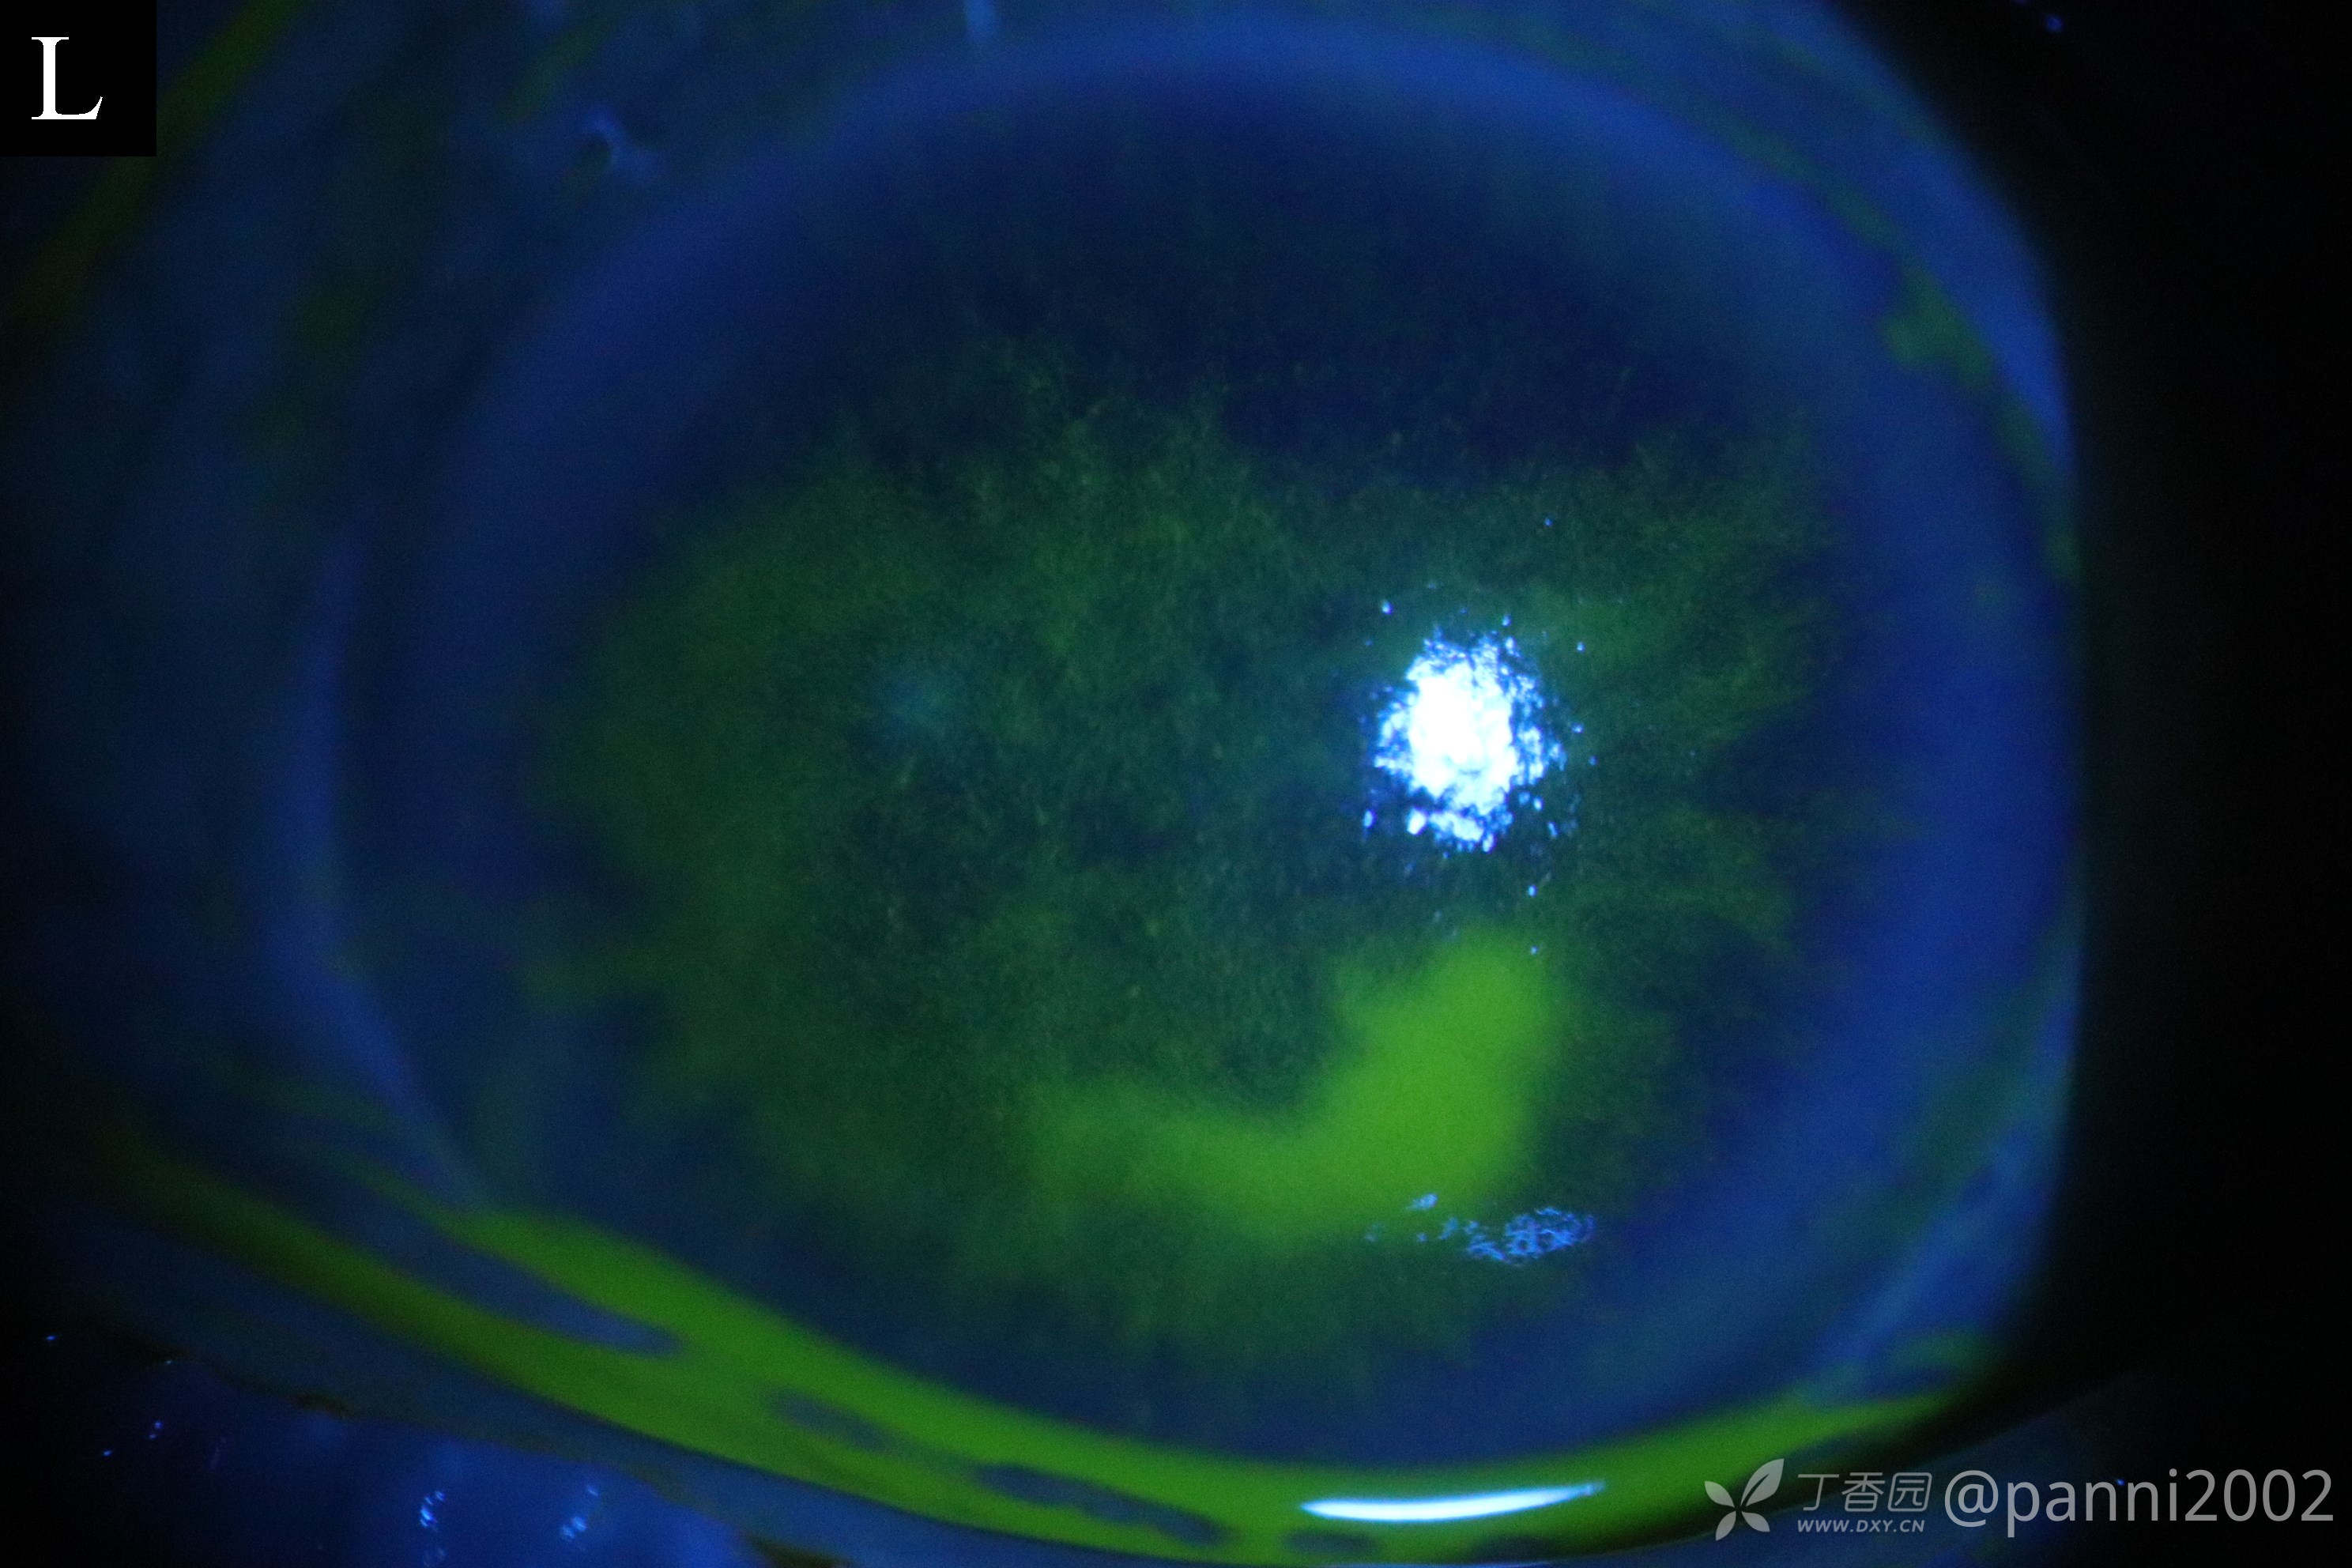

左眼白内障术后角膜水肿,内皮皱褶近1月

•80岁老年男性,2022.5.20在我科行左眼FLACS,手术顺利,术后第一天视力0.8,角膜透明,前房清亮。予 露达舒及贝复舒点眼,术后三天即2022.5.23诉眼痛、异物感,查左眼角膜上皮轻水肿、粗糙,内皮轻皱褶,KP(-),房水清亮。考虑干眼后上皮情况差,予加强局部贝复舒次数。即2022.5.28仍诉异常感、畏光、眼痛,视力下降,体查角膜水肿及内皮皱褶稍有加重,无KP及前房反应。调整贝复舒为 卡波姆,局部应用绷带镜减轻角膜刺激。

2022.6.19 反复上皮粗糙水肿,内皮皱褶,KP(-)。前房水清亮。

期间请一些国内确实角膜内皮炎的专家看了,从病程上看,像角膜内皮炎。用了抗病毒药物无明显效果。

还有专家说是典型的上皮功能障碍。但我觉得无法解释早期那么重的刺激病症,也无法解释持续存在、中途有加重的角膜内皮皱褶。